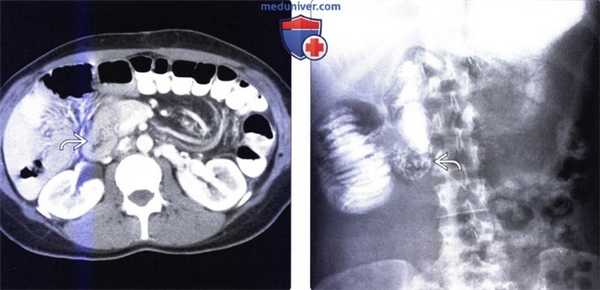

Мальротация кишечника (нонротация) у мужчины 39 лет.

(а, б) Тощая кишка — прямое продолжение двенадцатиперстной (стрелка, а), отсутствуют нормальные 3-й и 4-й сегменты двенадцатиперстной кишки, а также двенадцатиперстно-тощекишечный переход (звездочка, б).

(в, г) Петли тонкой кишки (прямые стрелки) лежат в левой половине брюшной полости, а ободочная кишка (изогнутые стрелки) — в правой половине. Заворот средней кишки у мальчика 11 лет.